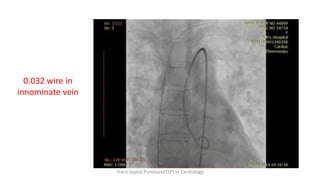

0.032 wire in

innominate vein

Trans Septal Puncture(TSP) in Cardiology

• 44.

0.032 wire in innominatevein Trans Septal Puncture(TSP) in Cardiology